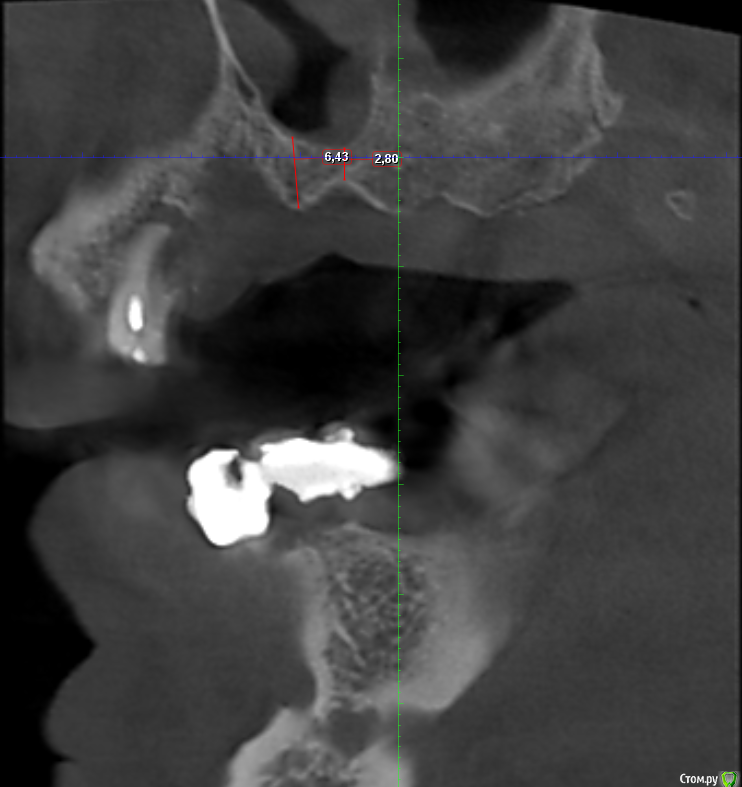

Serg2018 Опубликовано 28 ноября, 2018 Автор Поделиться Опубликовано 28 ноября, 2018 Вот пытаюсь выложить несколько срезов КТ правой стороны, надеюсь, я это правильно понял, делаю впервые. Также тыкал мышкой и она мне что-то замеряла, если в мм, то получается, что в самой тонкой части толщина 2,8 мм? или это я все неправильно понимаю? Ссылка на комментарий

Nazim_NV86 Опубликовано 28 ноября, 2018 Поделиться Опубликовано 28 ноября, 2018 (изменено) Sirona Galileos ?Должно быть окно, где срезы видны как распил. Сечение. Лучше на этом измерять. Можете всю томограмму загрузить на яндекс диск и выложить ссылку. Но сначала проверьте как работает запуск. На той программе, что выше написал, запуск скорее всего возможен только с диска. Если среди файлов на диске есть файл DCM, то его одного достаточно. Просмотрщик не нужно выкладывать. Изменено 28 ноября, 2018 пользователем Nazim_NV86 Ссылка на комментарий